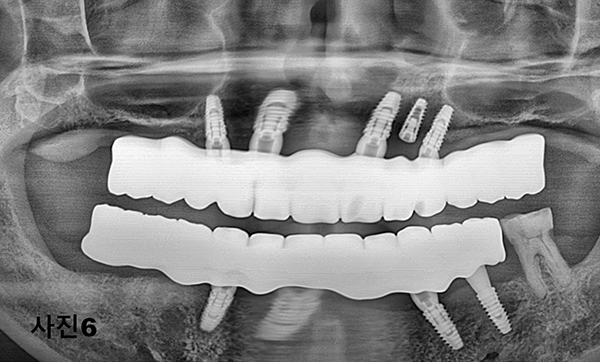

수술 당일 수면마취후 12개의 치아를 다 발치하고 상악에 5개 하악에 4개를 식립하고 (사진3) 왼쪽 마지막 어금니는 단단하여

살리면서 그 상태를 컴퓨터 스캐닝하여 본 병원에서 다음날 (사진4)와 같이 임시 고정성 보철물을 제작하여 심미적 기능과 저작기능을 제공하여 주었다.

5개월후에 영구적인 티타늄과 지르코니아 보철물이 구강내 장착된 (사진5)와 x-ray(사진 6)모습이다.